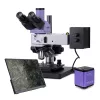

Seznamte se s digitálním mikroskopem MAGUS Bio D230TL LCD (40-1000x) skvělým řešením pro laboratorní, diagnostická a výzkumná pracoviště v oblasti hygieny, medicíny, farmacie a biotechnologie. Tento biologický mikroskop je vybaven trinokulární hlavou a energeticky úsporným LED osvětlením, které poskytuje stálou teplotu barev a dlouhou životnost (50 000 hodin). V základní konfiguraci umožňuje pozorování ve světlém poli, ale s volitelným příslušenstvím jej snadno rozšíříte o fázový kontrast, tmavé pole nebo polarizaci.

Sestava obsahuje digitální fotoaparát MAGUS CHD10 s Full HD rozlišením (1920x1080 px) a 60 snímky za sekundu, který poskytuje plynulý obraz bez zpoždění. Tento autonomní fotoaparát nevyžaduje PC ani software a připojuje se přímo přes HDMI k 13,3 IPS monitoru MAGUS MCD20.

Mikroskop disponuje achromatickými objektivy s korekcí na nekonečno a revolverovým nosičem pro 5 objektivů, z nichž čtyři jsou součástí balení. Trinokulární hlava s otočným mechanismem o 360° umožňuje snadné přizpůsobení uživateli. LED osvětlení (3 W) je stabilní a nezmění teplotu barev při nastavení jasu.

Klíčové vlastnosti mikroskopu MAGUS Bio D230TL LCD:

Zvětšení 401000x, možnost rozšíření až na 2000x

Trinokulární hlava s otočením o 360° a vertikálním tubusem pro digitální fotoaparát

Achromatické objektivy s korekcí na nekonečno pro jasný obraz bez aberací

LED osvětlení 3 W s dlouhou životností a stabilní teplotou barev

Abbeho kondenzor s možností připojení fázového kontrastu nebo tmavého pole

Koaxiální knoflíky hrubého a jemného zaostřování s aretací a nastavením tuhosti

Klíčové vlastnosti digitálního fotoaparátu MAGUS CHD10:

Full HD rozlišení (1920x1080 px) přes HDMI

60 snímků za sekundu pro plynulé zobrazení vzorků

Barevný CMOS snímač SONY Starvis s nízkým šumem a vysokou citlivostí

Samostatný provoz bez PC, záznam fotografií a videa na SD kartu

Klíčové vlastnosti monitoru MAGUS MCD20:

13,3 IPS displej s Full HD rozlišením

Široké pozorovací úhly (178°) a věrné barvy

Flexibilní umístění: stojan nebo přímé připojení k fotoaparátu

Obsah balení:

Digitální mikroskop MAGUS Bio D230TL LCD (40-1000x)

Digitální fotoaparát MAGUS CHD10

HDMI kabel (1,5 m), USB myš, SD karta 32 GB, napájecí adaptér, uživatelská příručka a záruční list

LCD monitor MAGUS MCD20

Trinokulární hlava

Achromatické objektivy: 4x/0,10; 10x/0,25; 40x/0,65 (odpružený); 100x/1,25 olej (odpružený)

Okuláry 10x/18 mm (2 ks), očnice (2 ks)

Abbeho kondenzor s nastavitelnou clonou a slotem pro fázový kontrast/tmavé pole

Filtry (4 ks)

Adaptér C-mount pro fotoaparát

Nádobka s imerzním olejem, protiprachová krytka, síťový napájecí kabel, uživatelská příručka a záruční list